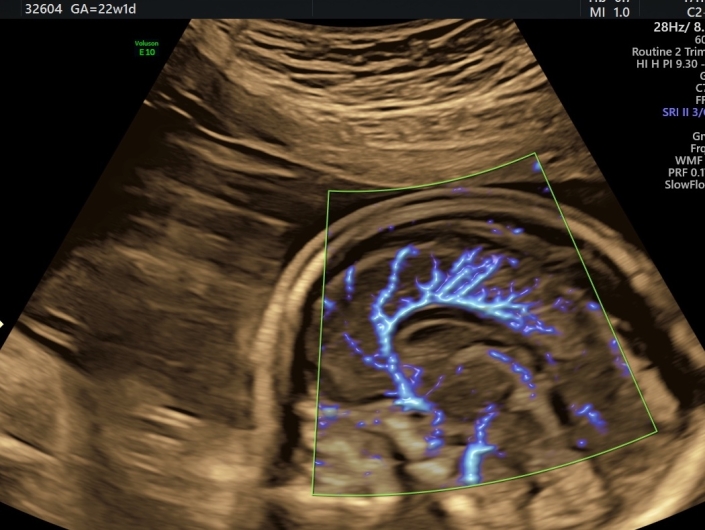

Das Angebot der erweiterten pränatalen Diagnostik in unserer Praxis erstreckt sich vom erweiterten Erst-Trimester-Screening mit Nackentransparenzmessung (lizenziert durch die FMF-London) und Hormondiagnostik (PAPP-A, f. ß-HCG), frühem Organultraschall und fetaler Echokardiographie, über die Feindiagnostik/Organultraschall im zweiten Trimester mit fetaler Echokardiographie und farbcodierter Doppleruntersuchungen bis hin zur invasiven Diagnostik mit Chorionzottenbiopsie (Mutterkuchenbiopsie) und Amniocentese (Fruchtwasserpunktion).

Mit dem Voluson E10 ® von GE steht uns ein modernes Hochleistungs-Ultraschallgerät zur Verfügung.

Das Voluson E10 ®, ein Produkt der GE-Expert-Serie, wurde speziell für die fortschrittliche und subtile Feindiagnostik in Gynäkologie und Pränatalmedizin entwickelt. Wo komplexe Fälle nicht die Ausnahme, sondern die Regel sind. Wo schwierige diagnostische Fragen tagtäglich zu lösen sind. Wo Patienten eine umfassende Information und Beratung erwarten.